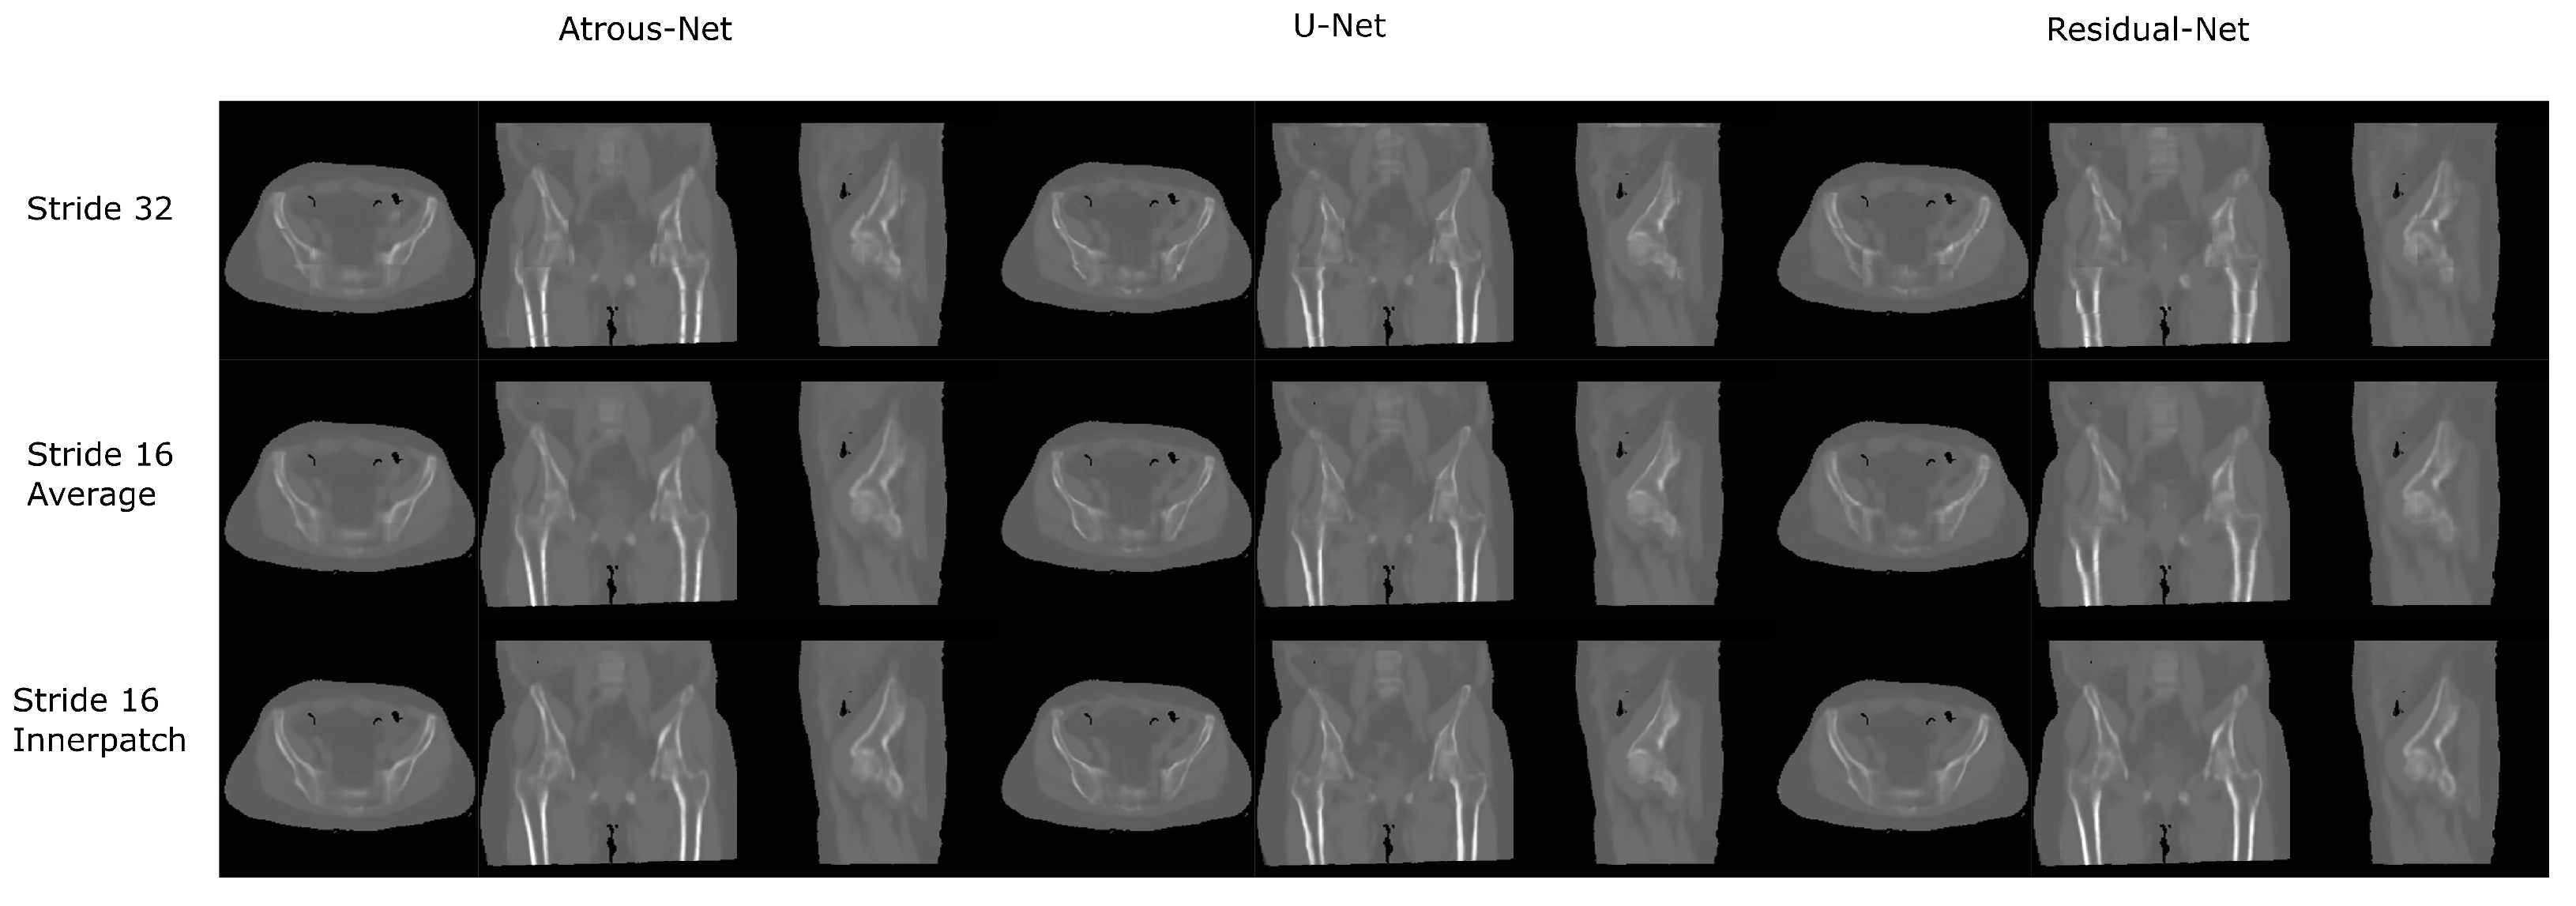

The results for all tissues using the pelvis dataset are depicted in Table 16, Table 17 and Table 18; the results using only the bone voxels are detailed in Table 19, Table 20 and Table 21; the results using only the fat voxels are detailed in Table 22, Table 23 and Table 24; and the results using only the soft-tissue voxels are detailed in Table 25, Table 26 and Table 27. In the pelvis dataset all networks performed very similar when all tissues were considered. However, 3D networks obtained slightly worse results when assessing bone alone and very similar results for all tissues. The best network in the bone dataset was the 2D Residual network that obtained a MAE of 201.56 HU, a PSNR of 23.20 and a Pearson Coefficient of 0.476 in the bone. Additionally, the error in bone with all networks increased when the 3D scheme was used. The ANOVA test for the 2D results reported a statistically significant effect of the networks in all tissues and bone MAE (all tissues: , ; bone: , ) and PSNR (all tissues: , , bone: , ). According to 3D results, the ANOVA test did not expose statistically significant differences when using different architectures on all tissue MAE (all tissues: , ; bone: , ) and PSNR (all tissues: , ; bone: , ). Post hoc Student’s t-test is depicted in Table 28 and Table 29. It reveals that the Residual-net and Atrous-net did not provide statistically significant differences. Visual result examples of pelvis pseudo-CTs are depicted in Figure 8 and Figure 9. Table 30 shows the time needed to synthesize a whole pelvis volume using the different architectures.

Figure 8.

Pelvis results using 2D networks.

Figure 9.

Pelvis results using 3D-16 networks.

3.4. 3D Reconstruction Results

Figure 10 and Figure 11 show the results of the three merging strategies that have been tested: stride 32, stride 16 with averaging of overlapping voxels and stride 16 considering the inner cube. The average time to synthesize a volume is shown in Table 15 and Table 30. The first method—referred as “stride 32” in Figure 10 and Figure 11—generated artifacts in the boundaries of the cube and misalignment in the bone and air structures. Moreover, this approach showed a greater error than the other two in the quantitative results. Nevertheless, this method was quite fast, generating a volume in 8–19 s. The other two methods provided, in average, a similar quantitative result, being the use of the inner cube slightly better. However, the use of stride 16 increased the time to generate a pseudo-CT volume up to 58–90 s. According to the averaging strategy, some artifacts can be noticed in the boundaries of the cubes after a visual inspection of the results.

Figure 11.

Comparison between the reconstruction method proposed.

In case the anatomy does not have complex structures across slices, 3D schemes are not the best option. Moreover, if the input image has very similar areas -as in pelvis acquisitions-, 3D patches will not satisfactory synthesize the pseudo-CT due to the lack of contextual information. In this scenario, according to our results, it would be better to use a 2D scheme. Specifically, the residual network obtained the best results in 2D (), which is consistent with the results in general computer vision, where 2D approaches are used [26,39].

In the pelvis dataset, the results were quite similar between networks, having differences in a range of 5% in the bone. This could be due to the input data used in the experiment: the Dixon-VIBE MRI. The Dixon-VIBE, as shown in Figure 2, does not depict the bone well. Moreover, it is fairly probable that the information to generate the pseudo-CT that it is contained in the image is low or moderate compared to T1 acquisitions (see Figure 1). That is, the networks gave similar results because the information that can be extracted from the input images is limited. However, Dixon-VIBE is the standard acquisition in PET attenuation correction and it is usually easier to have access to this type of acquisitions for the pelvis anatomy. Therefore, the type of network that is implemented does not have a great impact on the results.